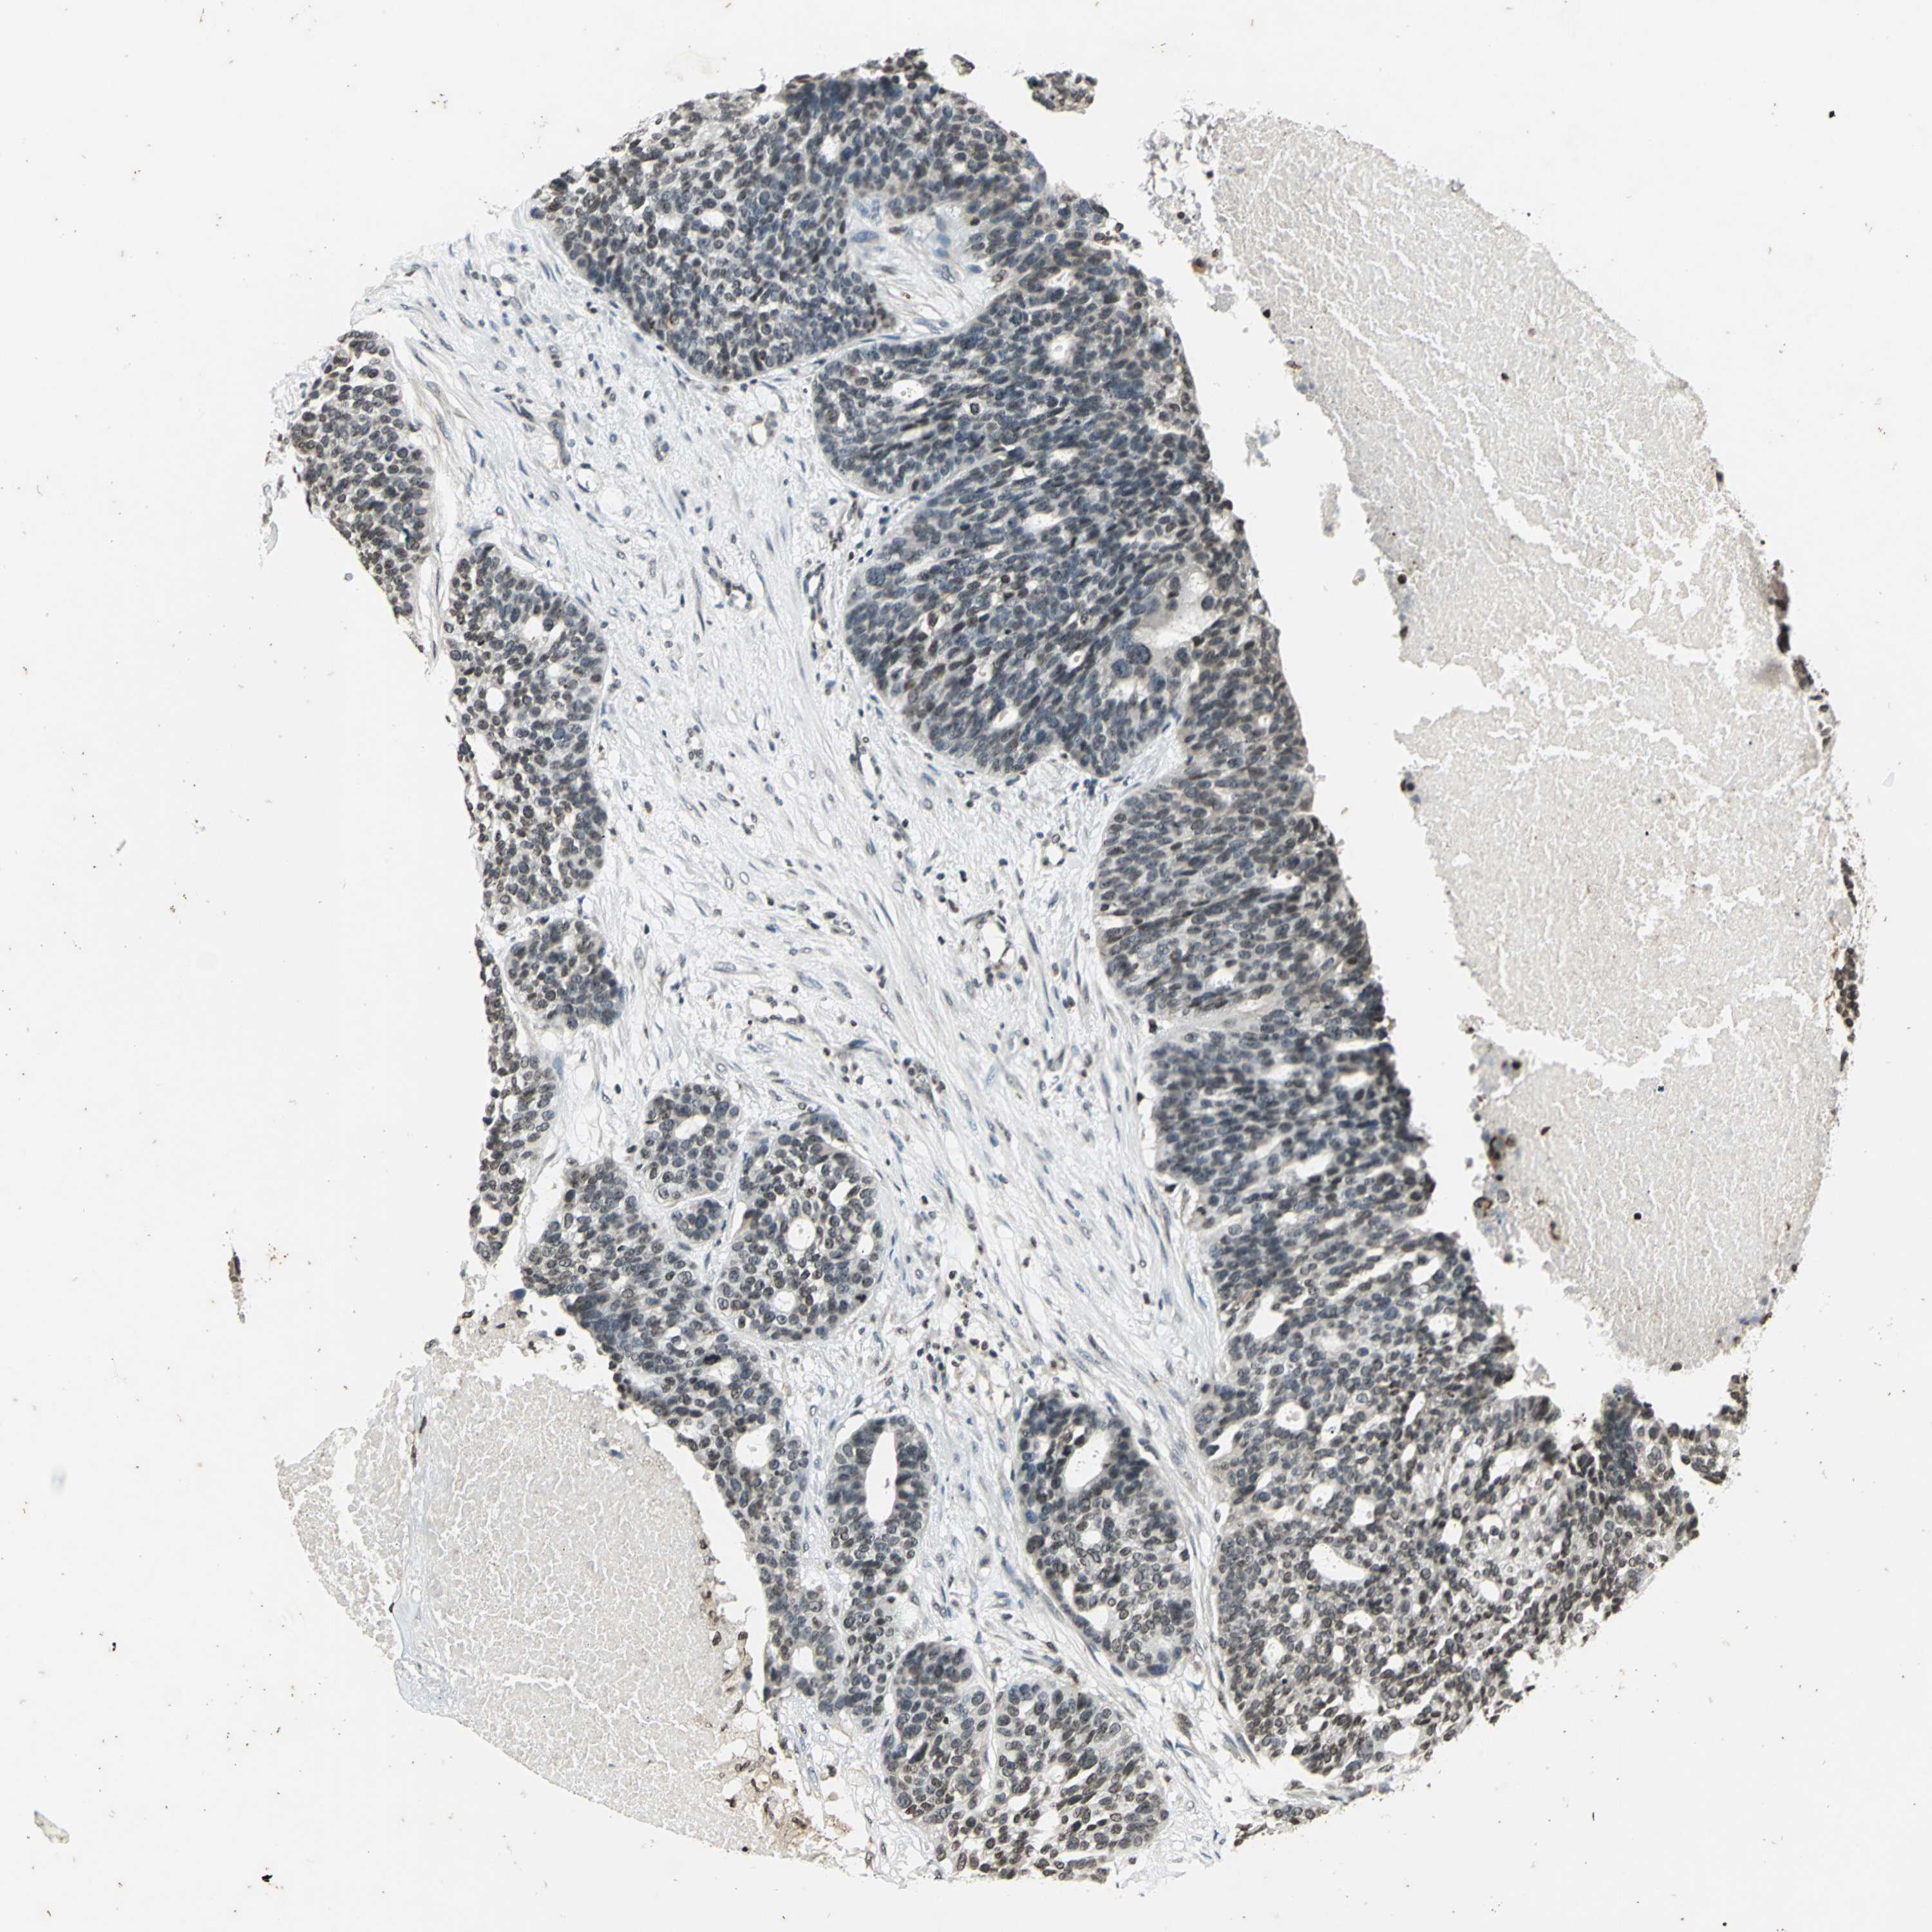

OVARIAN CANCER - Protein expressioni

A mouse-over function shows sample information and annotation data. Click on an image to view it in a full screen mode. Samples can be filtered based on level of antibody staining by selecting one or several of the following categories: high, medium, low and not detected. The assay and annotation is described here.

Note that samples used for immunohistochemistry by the Human Protein Atlas do not correspond to samples in the TCGA dataset.

Antibody stainingi

Antibody staining in the annotated cell types in the current human tissue is reported as not detected, low, medium, or high, based on conventional immunohistochemistry profiling in selected tissues. This score is based on the combination of the staining intensity and fraction of stained cells.

Each image is clickable and will lead to virtual microscopy that enables deeper exploration of all samples and also displays staining intensity scores, fraction scores and subcellular localization as well as patient and tissue information for each sample.

Antibody HPA003162

Antibody CAB005191

Cystadenocarcinoma, mucinous, NOS

Carcinoma, endometroid

Cystadenocarcinoma, serous, NOS

Carcinoma, NOS